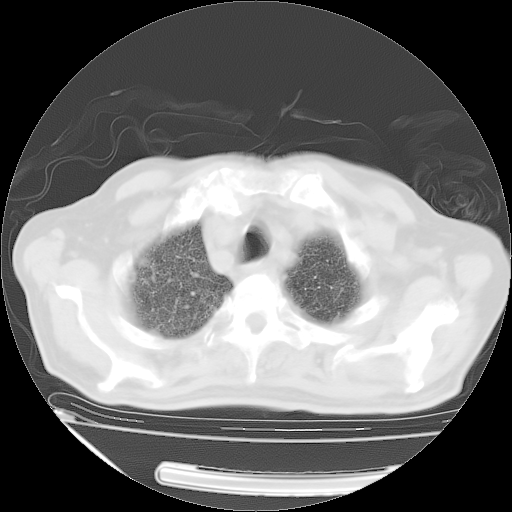

甲强龙80mg/日+抗结核治疗(异烟肼+利福霉素+乙胺丁醇)10天。复查肺部CT。

治疗10天肺部CT

仔细阅读病史资料和CT,我觉得两肺粟粒结核要高度怀疑。

今天带四次肺CT片到市医院,影像科4~5个主任都认为不考虑粟粒性肺结核。主要理由是在3月19日、4月2日、4月27日的CT片没有见到确切异常(肺结核)影像。影像科主任们建议找呼吸内科主任,呼吸内科主任认为首先考虑粟粒性肺结核。